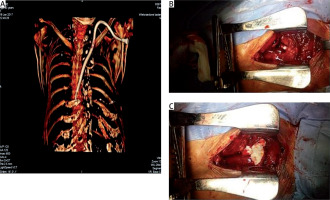

Figure 2

A – CT of the chest 3D reconstruction. B – Injury of the left brachiocephalic vein by a dialysis catheter. C – Sutured vessel, covered by a TachoSil hemostatic sponge